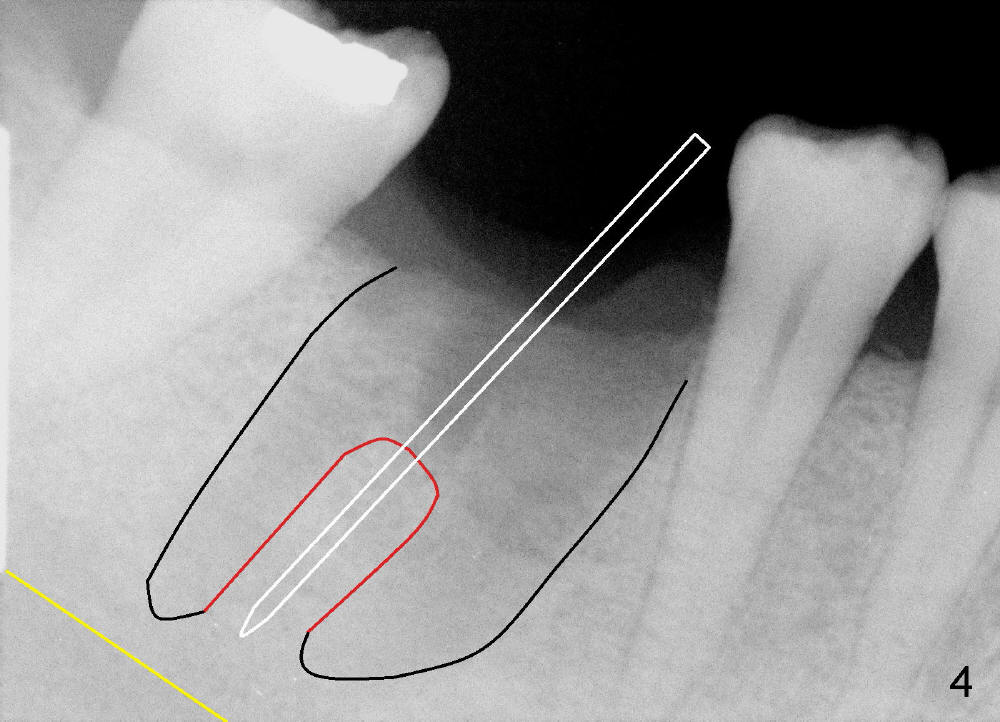

A 43-year-old lady had the lower right first molar extracted in other office last month. The socket appears to be healing normally (Fig.1). Tatum tapered implant 6x17 mm is planned (Fig.2). The implant is to be placed inside the septum (Fig.3 red outline; black: mesial and distal sockets; yellow: the upper border of the inferior alveolar canal). Either 1.5 mm pilot drill or 2 mm RT is used to start osteotomy in the septum at the depth of 17 mm (Fig.4 white outline). The osteotomy is enlarged with alternating use of osteotomes and 17 mm series tapered drills or Bicon reamers if autogenous bone will be needed (Fig.5 black), while the septal bone is pushed mesiodistally (arrows). After application of taps, an appropriately sized implant is placed (Fig.6 white). The septal bone continues expanding (arrows), whereas the mesial and distal sockets are being decreased.